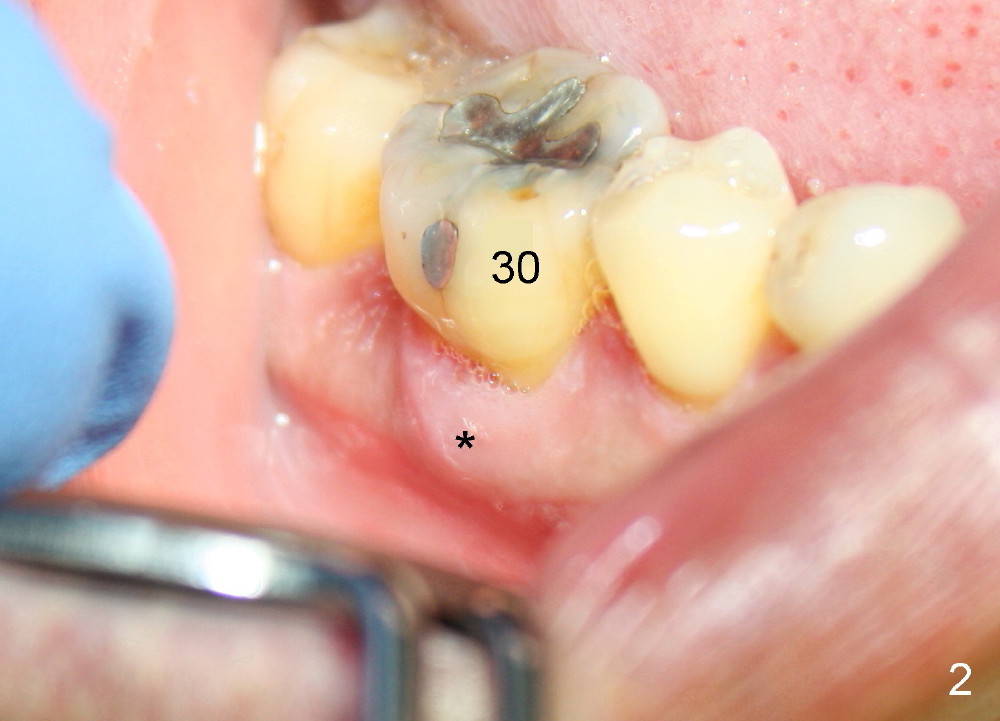

A 47-year-old man has had perio infection in the lower right 1st molar twice (Fig.1,2). Buccal and lingual furca pockets are ~ 9 mm. Following extraction and sectioning the septum, the osteotomy is initiated with a 2 mm pilot drill (Fig.3). Although the drill deviates into the mesial socket, the coronal end is controlled more or less in the middle of the edentulous area (compare white and red lines). Ideally the axis of the osteotomy (Fig.4 red line) should be parallel to that of the 2nd molar and perpendicular to the curve of Spree. The coronal end of the 3.5 mm reamer (Fig.5) and of the 7x17 mm tap (Fig.6 T) remains in the center of the edentulous space. The apical threads of the tap are engaged into the bone for stability (Fig.6 <). When 7x17 mm implant is placed with > 60 Ncm, the mesial socket is obliterated while the density of the distal one increases because of autogenous bone grafting (Fig.7*).